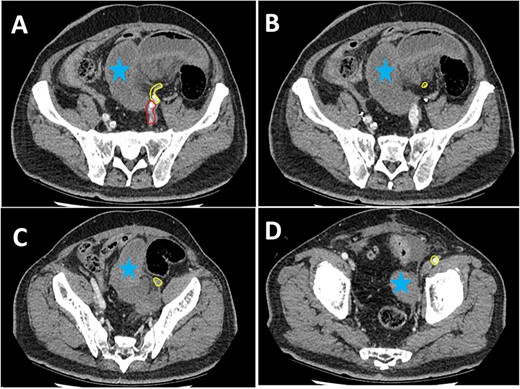

Histopathological examination confirmed ischaemic enteritis with patchy mural necrosis. Post-operative CT demonstrated healthy small bowel and patent left EIA (Figs 2 and 4). The patient recovered well and was discharged after a short hospital admission, with no ongoing abdominal symptoms or lower limb claudication. Follow up in the community was unremarkable with no further interventions required.

Post-operative CT scan. Series of sagittal images progressing from most medial (image A) to most lateral (image C). The patent EIA has been highlighted in yellow. Surgical clips are noted in image B (red arrow). Normal small bowel is noted in all images (blue stars).